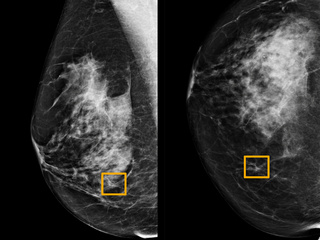

"Scientists at Drexel University, working with the centre, developed a hand-held, wireless breast cancer scanner, called the iBreast Exam. This device will enable any doctor or health care worker to conduct an exam within five minutes, and then access the results on a smartphone or tablet," Pritzeker said in her address to the 'Future of Urban Innovation Summit' in New York.